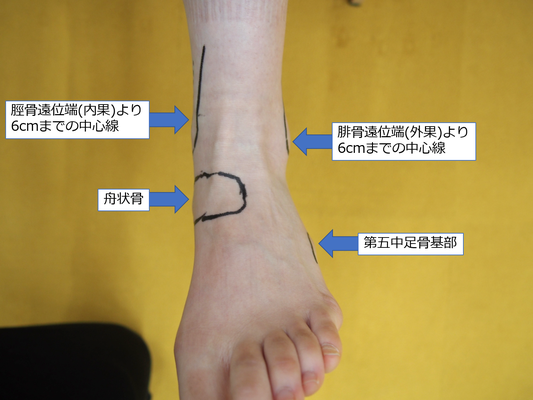

足首の捻挫か骨折か判断 オタワ足関節ルール バッファロールール 鍼灸スポーツ整体アスイク 尼崎 塚口 武庫之荘 伊丹 美容鍼 酸素カプセル パーソナルトレーニングダイエット

足首の捻挫か骨折か判断 オタワ足関節ルール バッファロールール 鍼灸スポーツ整体アスイク 尼崎 塚口 武庫之荘 伊丹 美容鍼 酸素カプセル パーソナルトレーニングダイエット

足首の捻挫で骨折してる してない の判断の指標 高石市東羽衣の阪本整骨院

足首の捻挫で骨折してる してない の判断の指標 高石市東羽衣の阪本整骨院